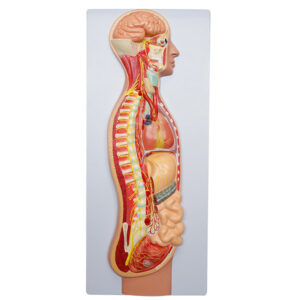

Modelo de Sistema Nervoso Autônomo